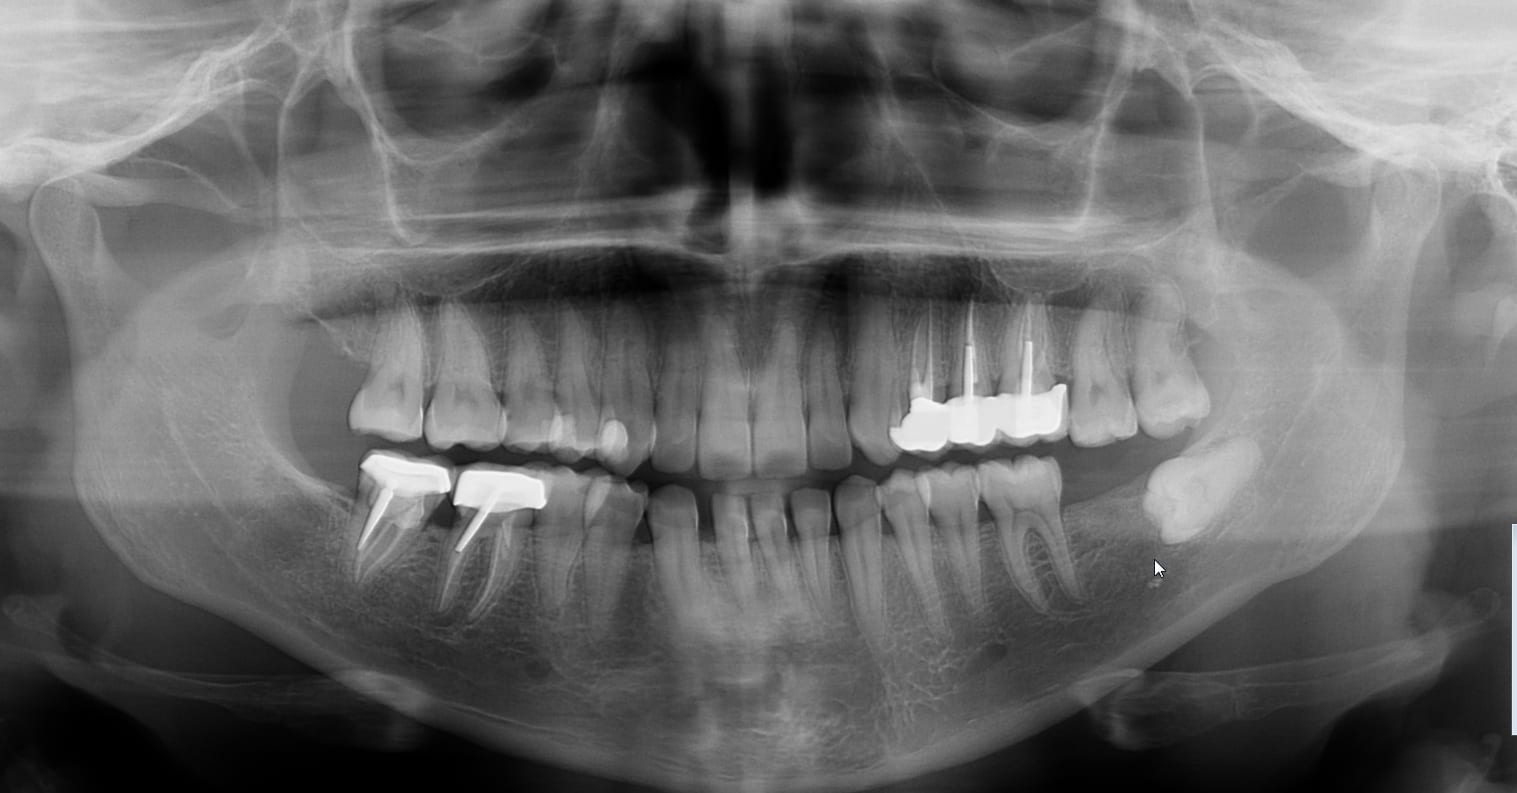

De l'impossibilité d'établir un plan de traitement à partir d'une panoramique.

J'aurai mis ma main à couper, en regardant la pano, que la 15 était dépulpée.

Et non.

Entre la pano et la rétroalvéolaire, j'ai seulement réalisé les extraction et posé un CVI sur la 15.

Je ne sais pas si tous tes clichés panoramiques sont du même acabit, mais je trouve que l'image manque singulièrement de précision... Beaucoup de bruit et pas net du tout!

C'est quoi la marque cette pano?

Sirona ORTHOPHOS XG installée en 2015, gérée depuis le module d'imagerie de Julie.

Sirona...

Soit il y a un problème de réglage et il faut rappeler le distributeur qui te l'a installé, soit il faut qu'ils arrêtent de fabriquer des appareils de radiologie...

On ne voit aucune ligne de manière nette, les dents ne sont pas bien individualisées, et paraissent comme ankylosées (on ne voit pas le desmodonte...). C'est pas nette du tout!

Une bonne pano doit te permettre de voir les différentes structures dentaires (émail, dentine, etc) et péridentaires (le desmondonte notamment), les caries, etc...

Cela ne m’étonne pas que tu puisses voir une obturation là où il n'y en a pas... Rien n'est bien délimité dans ta pano.

Pano : carie D de la 15 visible